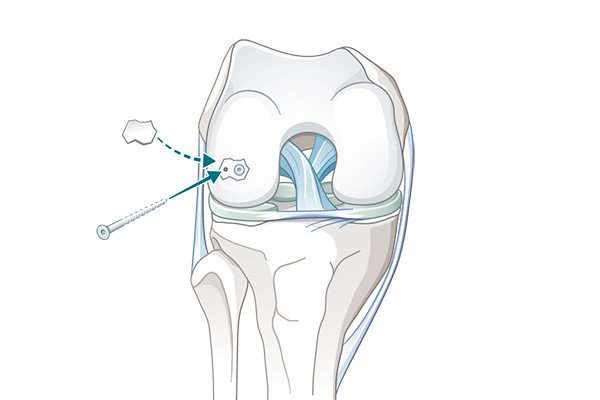

Abhängig von der Grösse des herausgeschlagenen Stücks bieten sich verschiedenste Refixationsmethoden an. Wir favorisieren zum aktuellen Zeitpunkt kleine Zuckerschrauben (Polypin), mit welchen das Stück wie ein Backstein im Bett einfach und stabil fixiert werden kann. Diese Minischrauben lösen sich dann im Verlauf selbst auf. Eine weitere Operation zum Entfernen der Schrauben ist nicht notwendig.